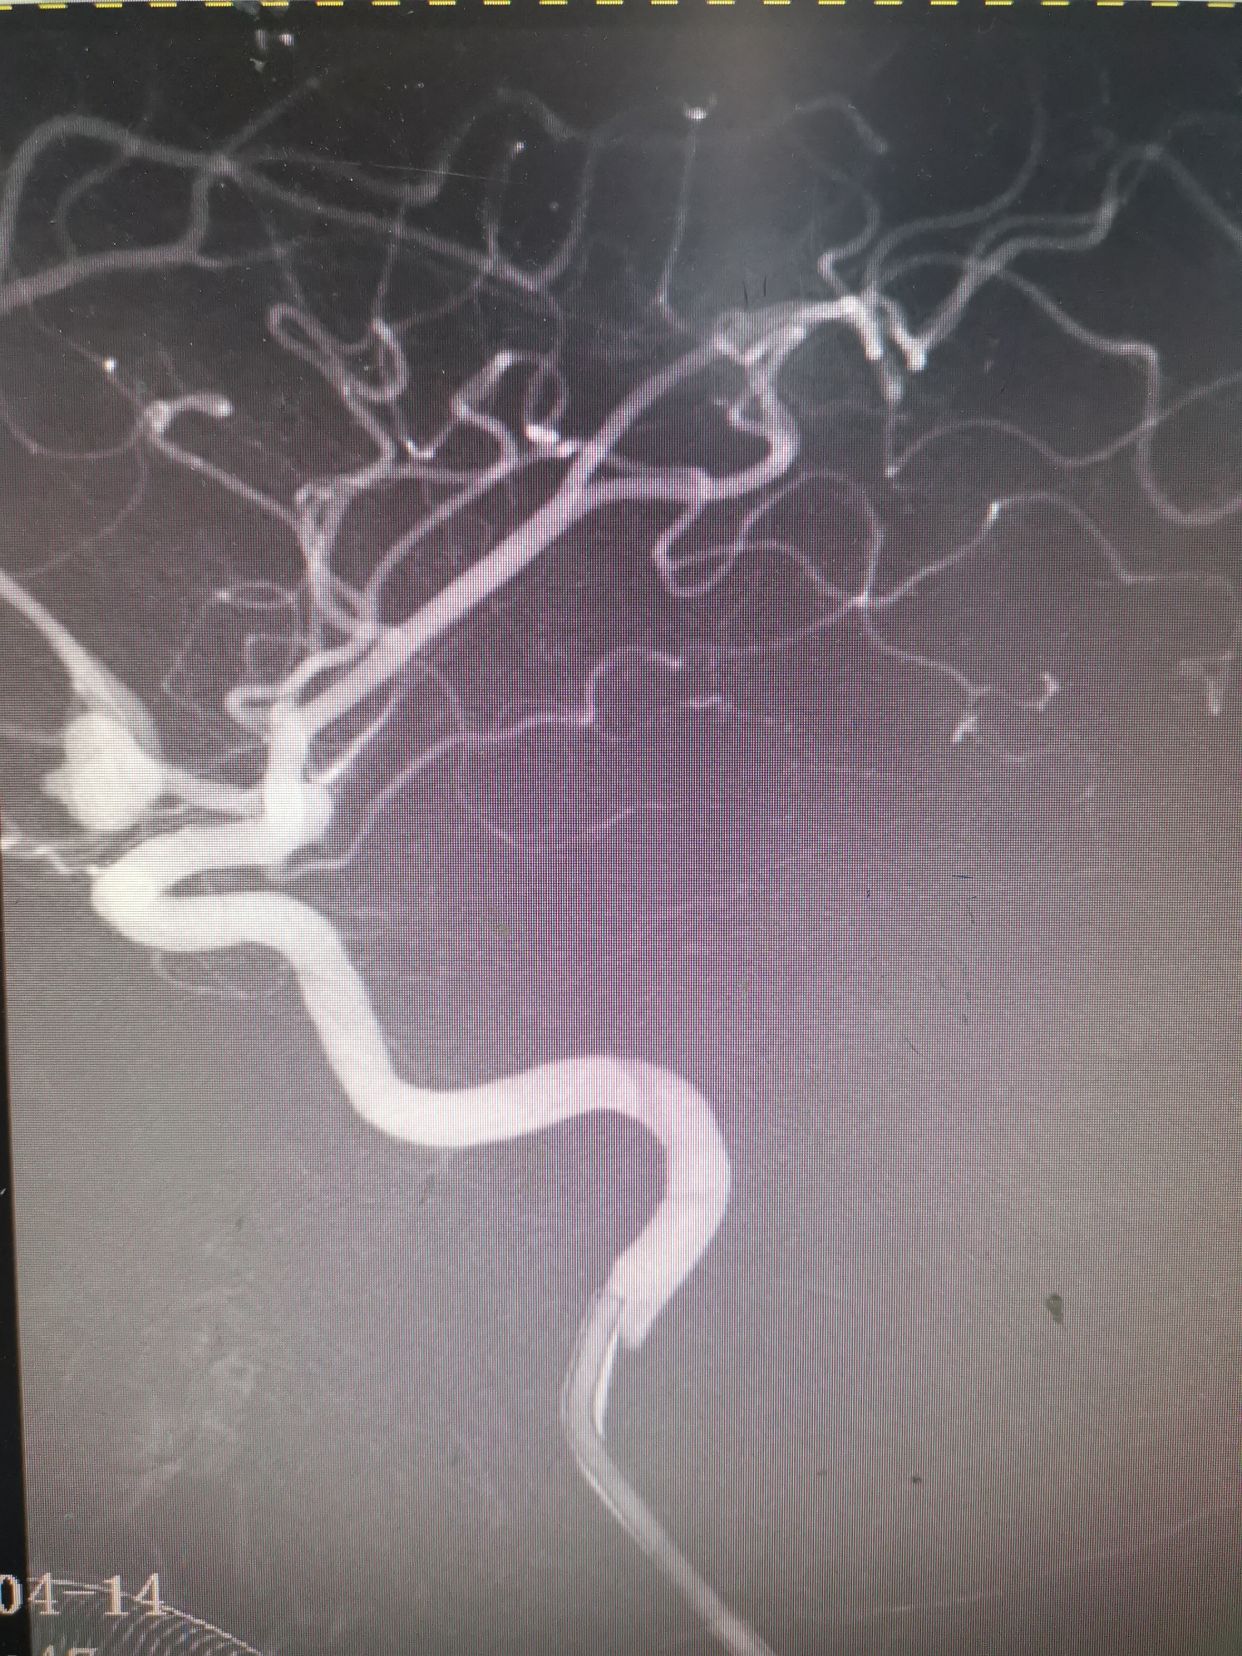

右侧颈内动脉造影。